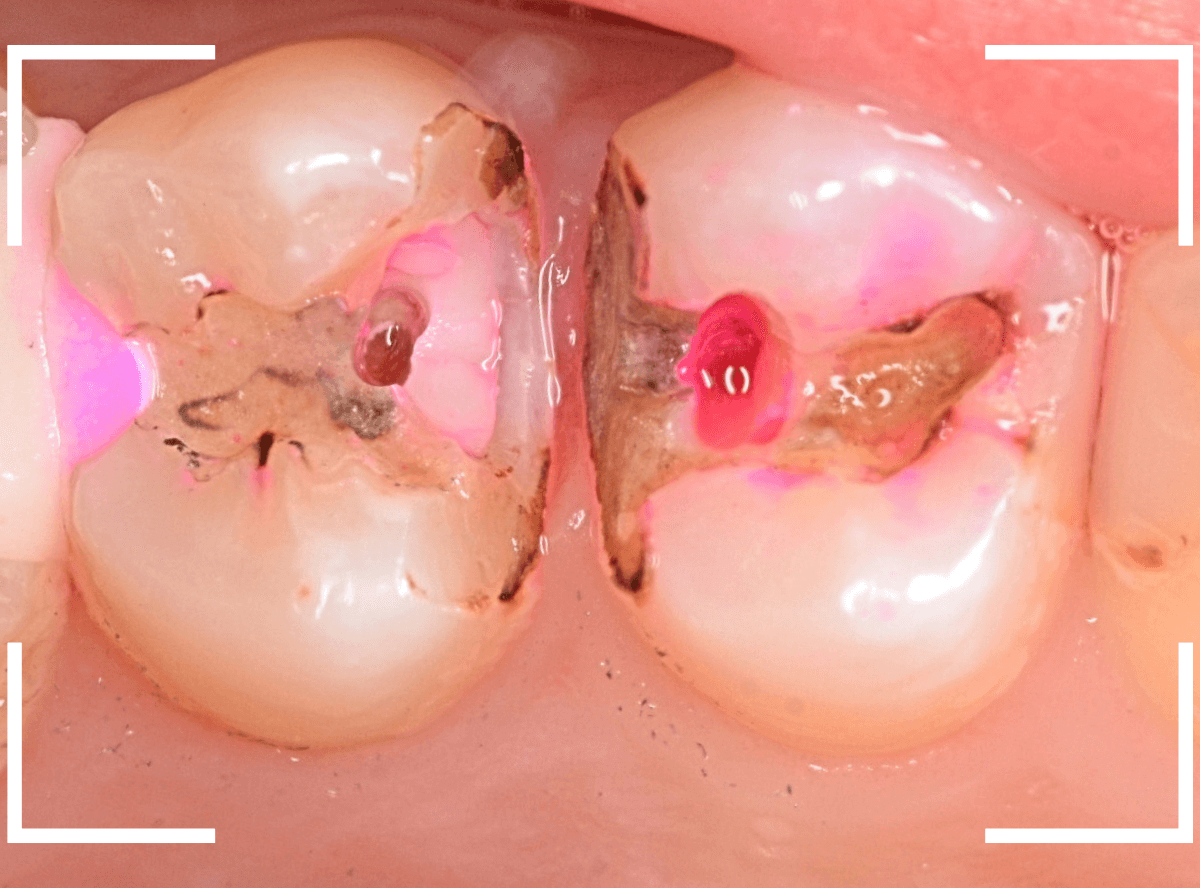

Case.1 隣り合った2本が大きな虫歯

「下の歯の奥から2番目の歯が痛む」という患者さんです。

お口の中を拝見すると、何だか1番奥の歯も怪しそうなので、歯を叩いて症状を確認してみます(打診)。

やっぱり奥から2番目の歯が痛むけど、1番奥の歯も少し痛むそうです。

レントゲン写真で確認してみました。

やはりどちらの歯も大きな虫歯でした。

2番目の歯が痛みの原因なのかもしれませんが、1番奥の歯の可能性も大いにあります。

両方の歯が原因かもしれません。

いずれにせよ、両歯とも痛みを神経に近い虫歯ですので、神経が炎症を起こして本格的な痛みになる前に治療をして神経の治療(抜髄)にならない可能性を少しでも上げたいところです。

通常であれば、初診時に大きな虫歯治療を2本行う時間的な余裕もありませんので、患者さんに事情を説明して後日治療になるのですが、今回は、予約時間よりも余裕をもって早めに来院していただいた患者さんだったので、何とか当日治療まで進める事ができました♪

まずは、麻酔をしてつめ物を慎重に外してみます。

両歯とも、色々嫌な予感のする所見です。

虫歯を可視化する、「う蝕検知液」で染め出ししてみます。

赤く染まっている場所が虫歯で、濃く染まっているところほど、虫歯は深いです。

手前の歯は一部神経が見えそうなところまで虫歯が来ていました(●部)。

患者さんのおっしゃるように、この歯が痛みの原因だったのかもしれません。

後ろの歯も、幸い神経は見えていませんが、かなり広く深い虫歯で心配な状況です。

急いで、神経を保護する薬を入れた後に、セメントで蓋をして経過観察します。

ほとんどの方はこれで何とかなりますが、痛みが出てしまい、神経の治療が必要になる方もいます。

神経の治療をすると歯の寿命は短くなってしまうので、できるだけ避けたいところです。

慎重に経過観察します。